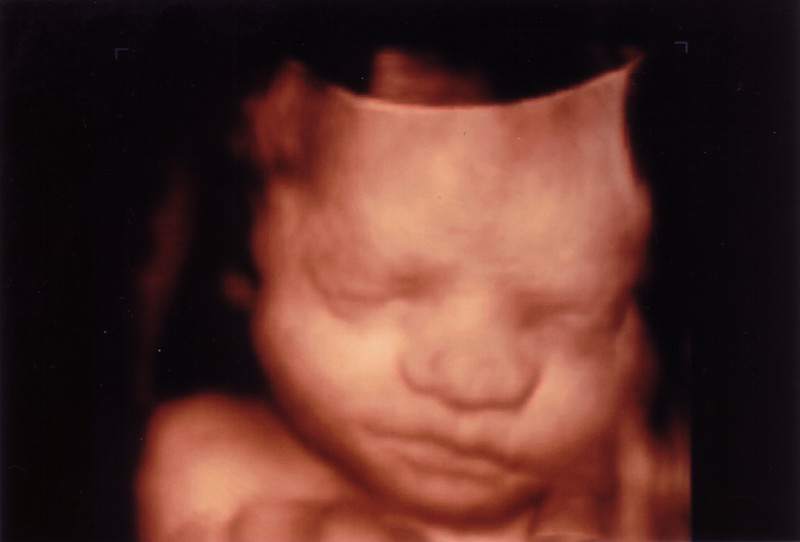

Lors de l'échographie en 3D, l'image est colorisée artificiellement en rose pour la rendre plus réaliste"Elle n'a pas tout à fait la même forme que le bébé" prévient Danièle Combourieu, car "la sonde que l'on tourne sur le ventre de la maman est beaucoup plus large pour contenir le capteur"En somme, il prend plusieurs plans et la machineMommy's Bundle of Joy Es un estudio en el que las mujeres embarazadas y sus familiares pueden ver el periodo de gestación para descubrir el género del bebé que está por nacer, así como su etapa de crecimiento También ofrecemos información para tener unA pioneer in the use of 3D4D technology in Quebec, Hugues Normand is the elite when it comes to specialised 3D4D technicians He has been practicing his profession for close to 10 years, and with the knowledge and techniques he's developed over time, he's acquired the experience it takes to be able to offer you the most beautiful and precise 3D4D images of your baby

Entre 25 et 30 semaines J'ai fait une echo 3d dans le mois d'aout a 27 semaines et personnellement jai adoré l'experienceils m'avaient conseillé de venir entre 25 et 30 semaines pour pouvoir le voir en entier J'avais beaucoup de crainte quelle ne soit pas encore beaucoup formé mais HO MON DIEUon voit meme a quoi elle va ressemblé on voit toutC'est3D/4D ultrasound provides beautiful images for you and your family It allows you to view and keep images of your baby before he or she is born!Echographie 3D 4D affective / plaisir dans les Alpes Maritimes Var PACA 2237 160 Rue Buffon, Le Cannet, France